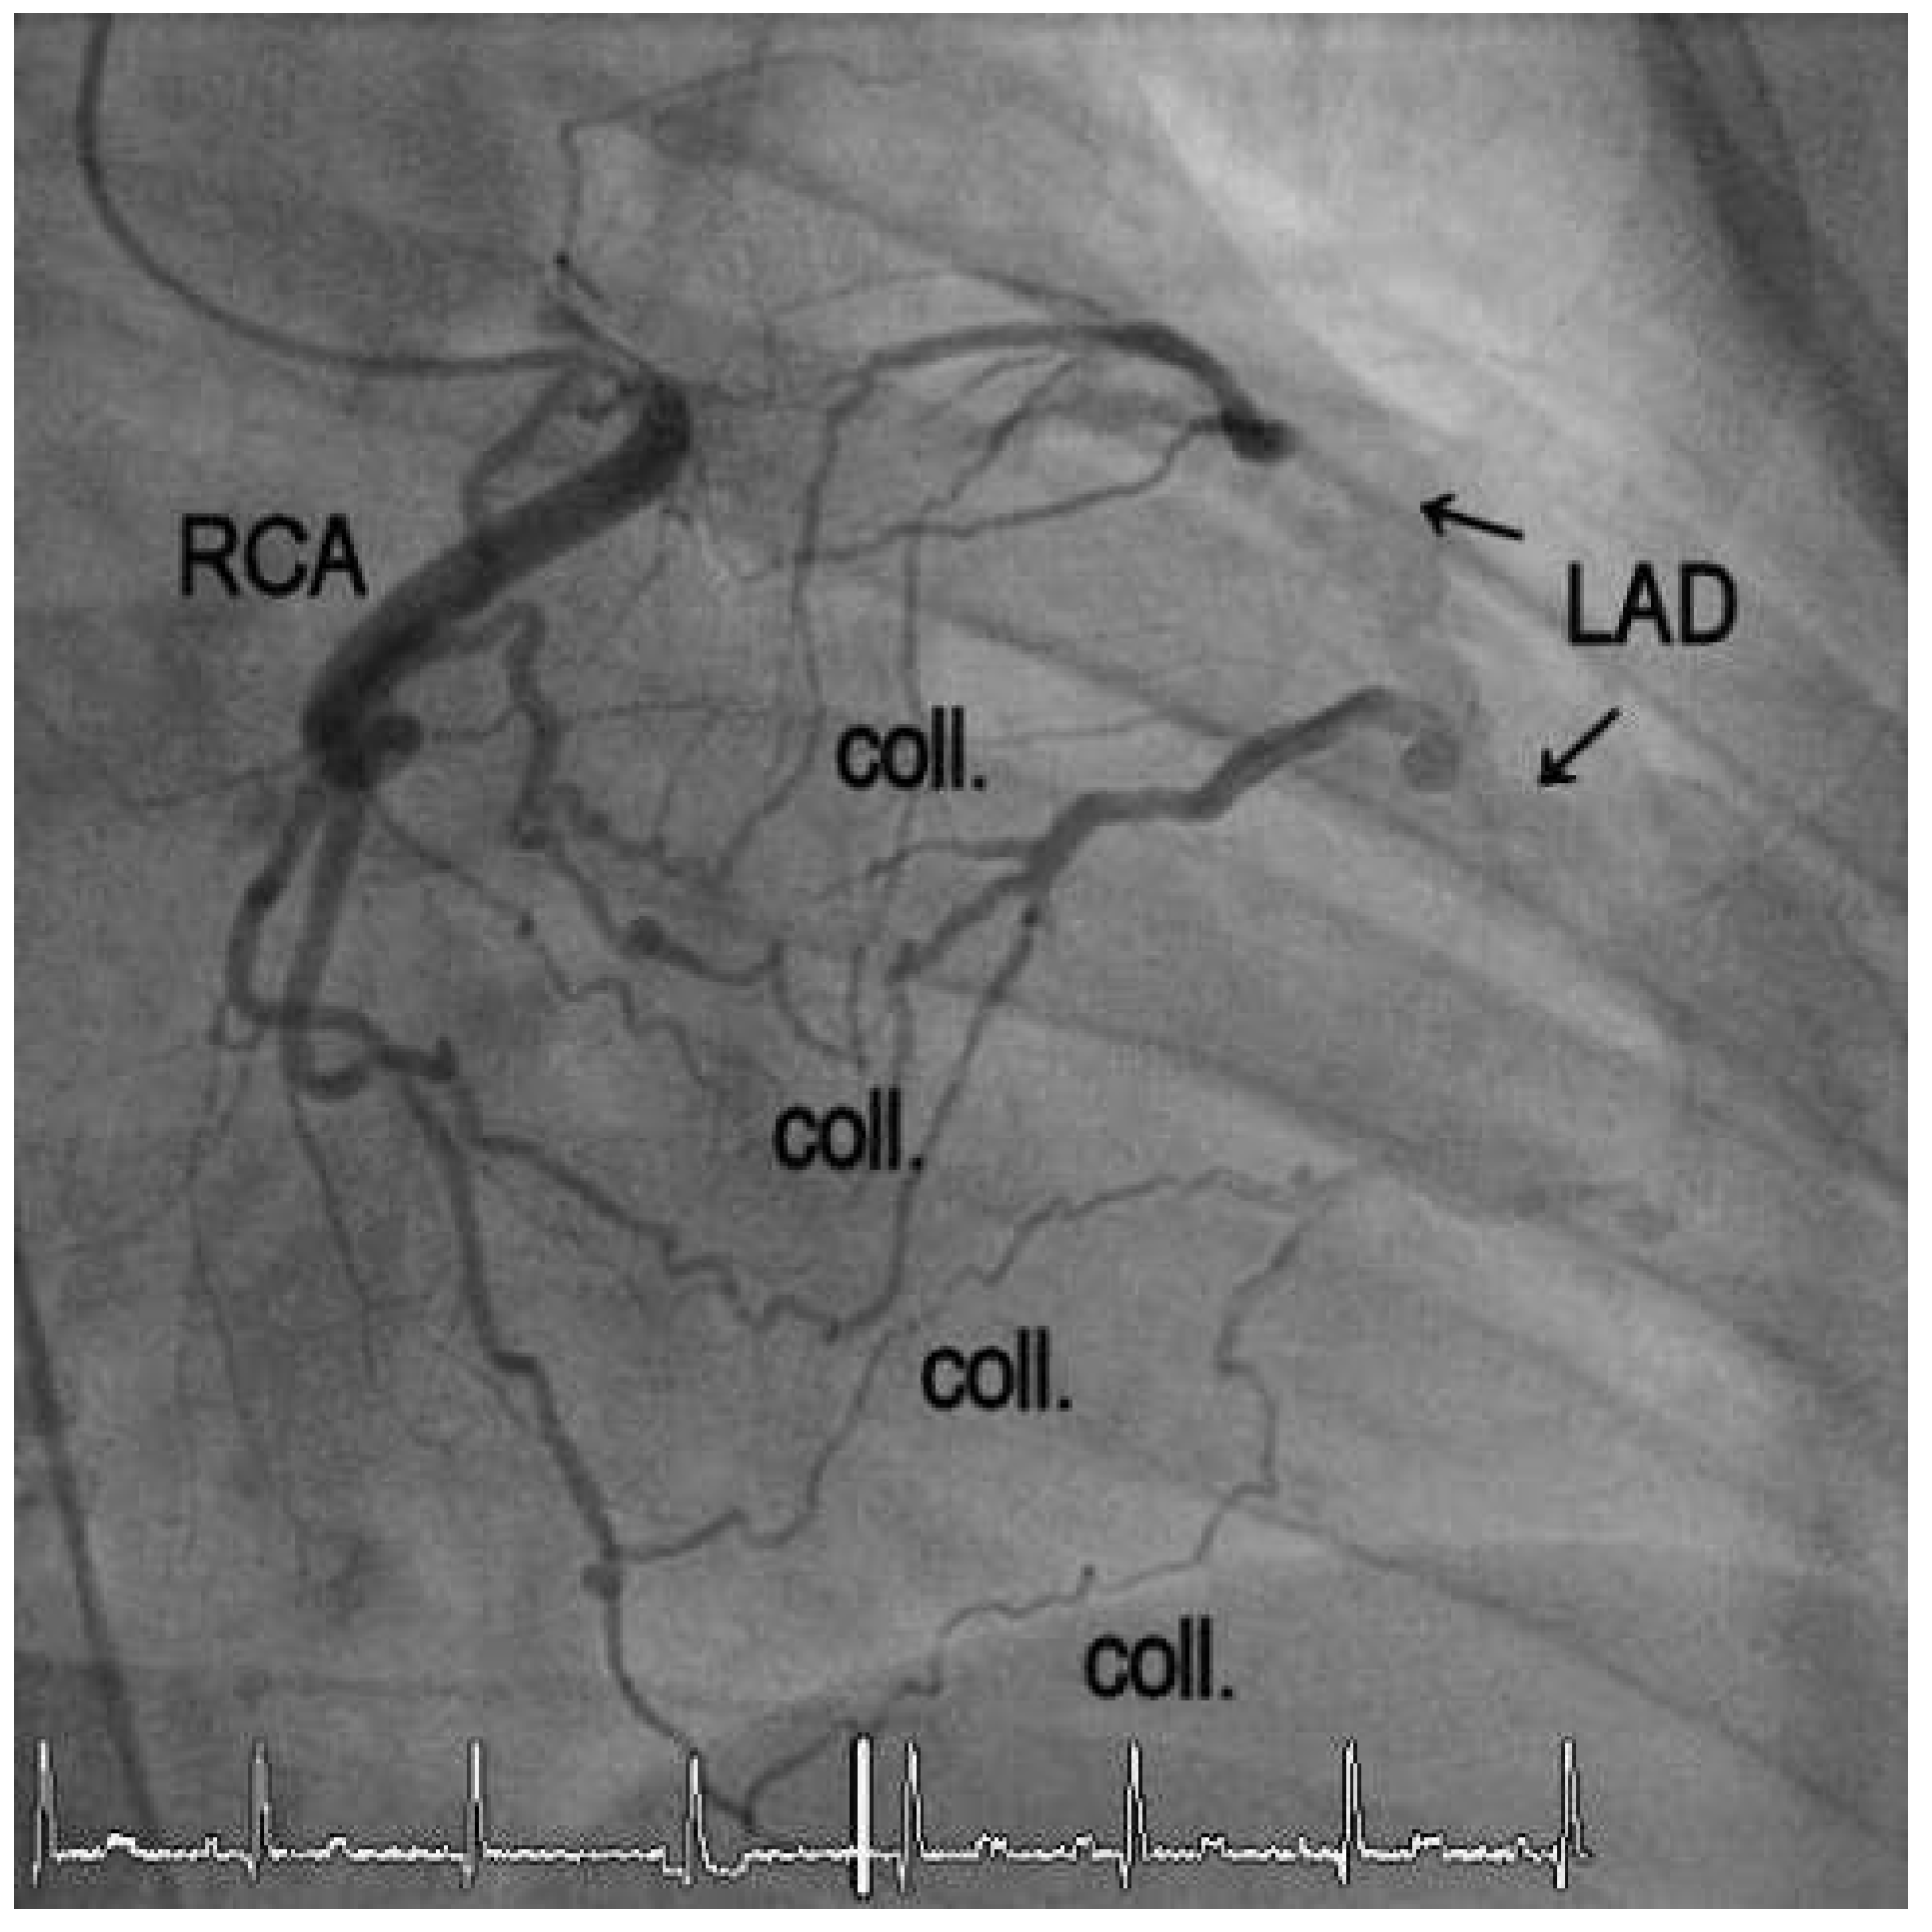

1. Case Report